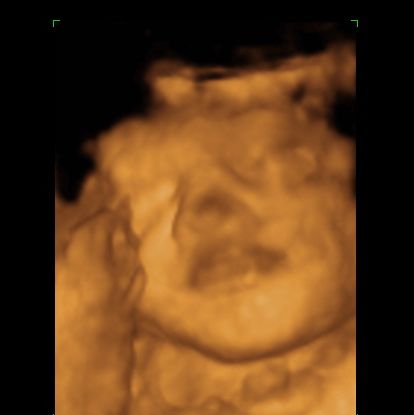

3d/4d sono yesterday w/pics...

I had it done at Impact. The baby wasnt really in the best position, so it was hard to get good shots of him, but it was still a great experience...

Image Attachment(s):